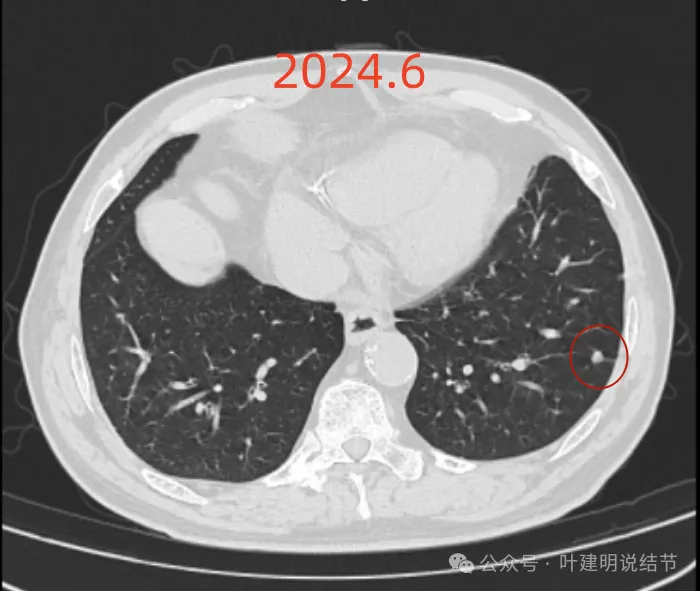

再看2024年6月时的影像:

右上没有明显变化,仍考虑良性可能性大。